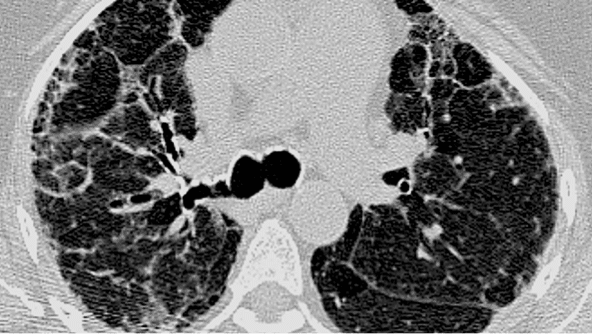

Exemplu de model cHP pe HRCT

Îngroșarea reticulară subpleurală, hiperinflație pulmonară și bronșiectazii de tracțiune

ASPECT PIINS - NSIP

Exemplu de model PIINS pe HRCT

Opacități cu aspect de sticlă mată, cruțare subpleurală și bronșiectazii de tracțiune